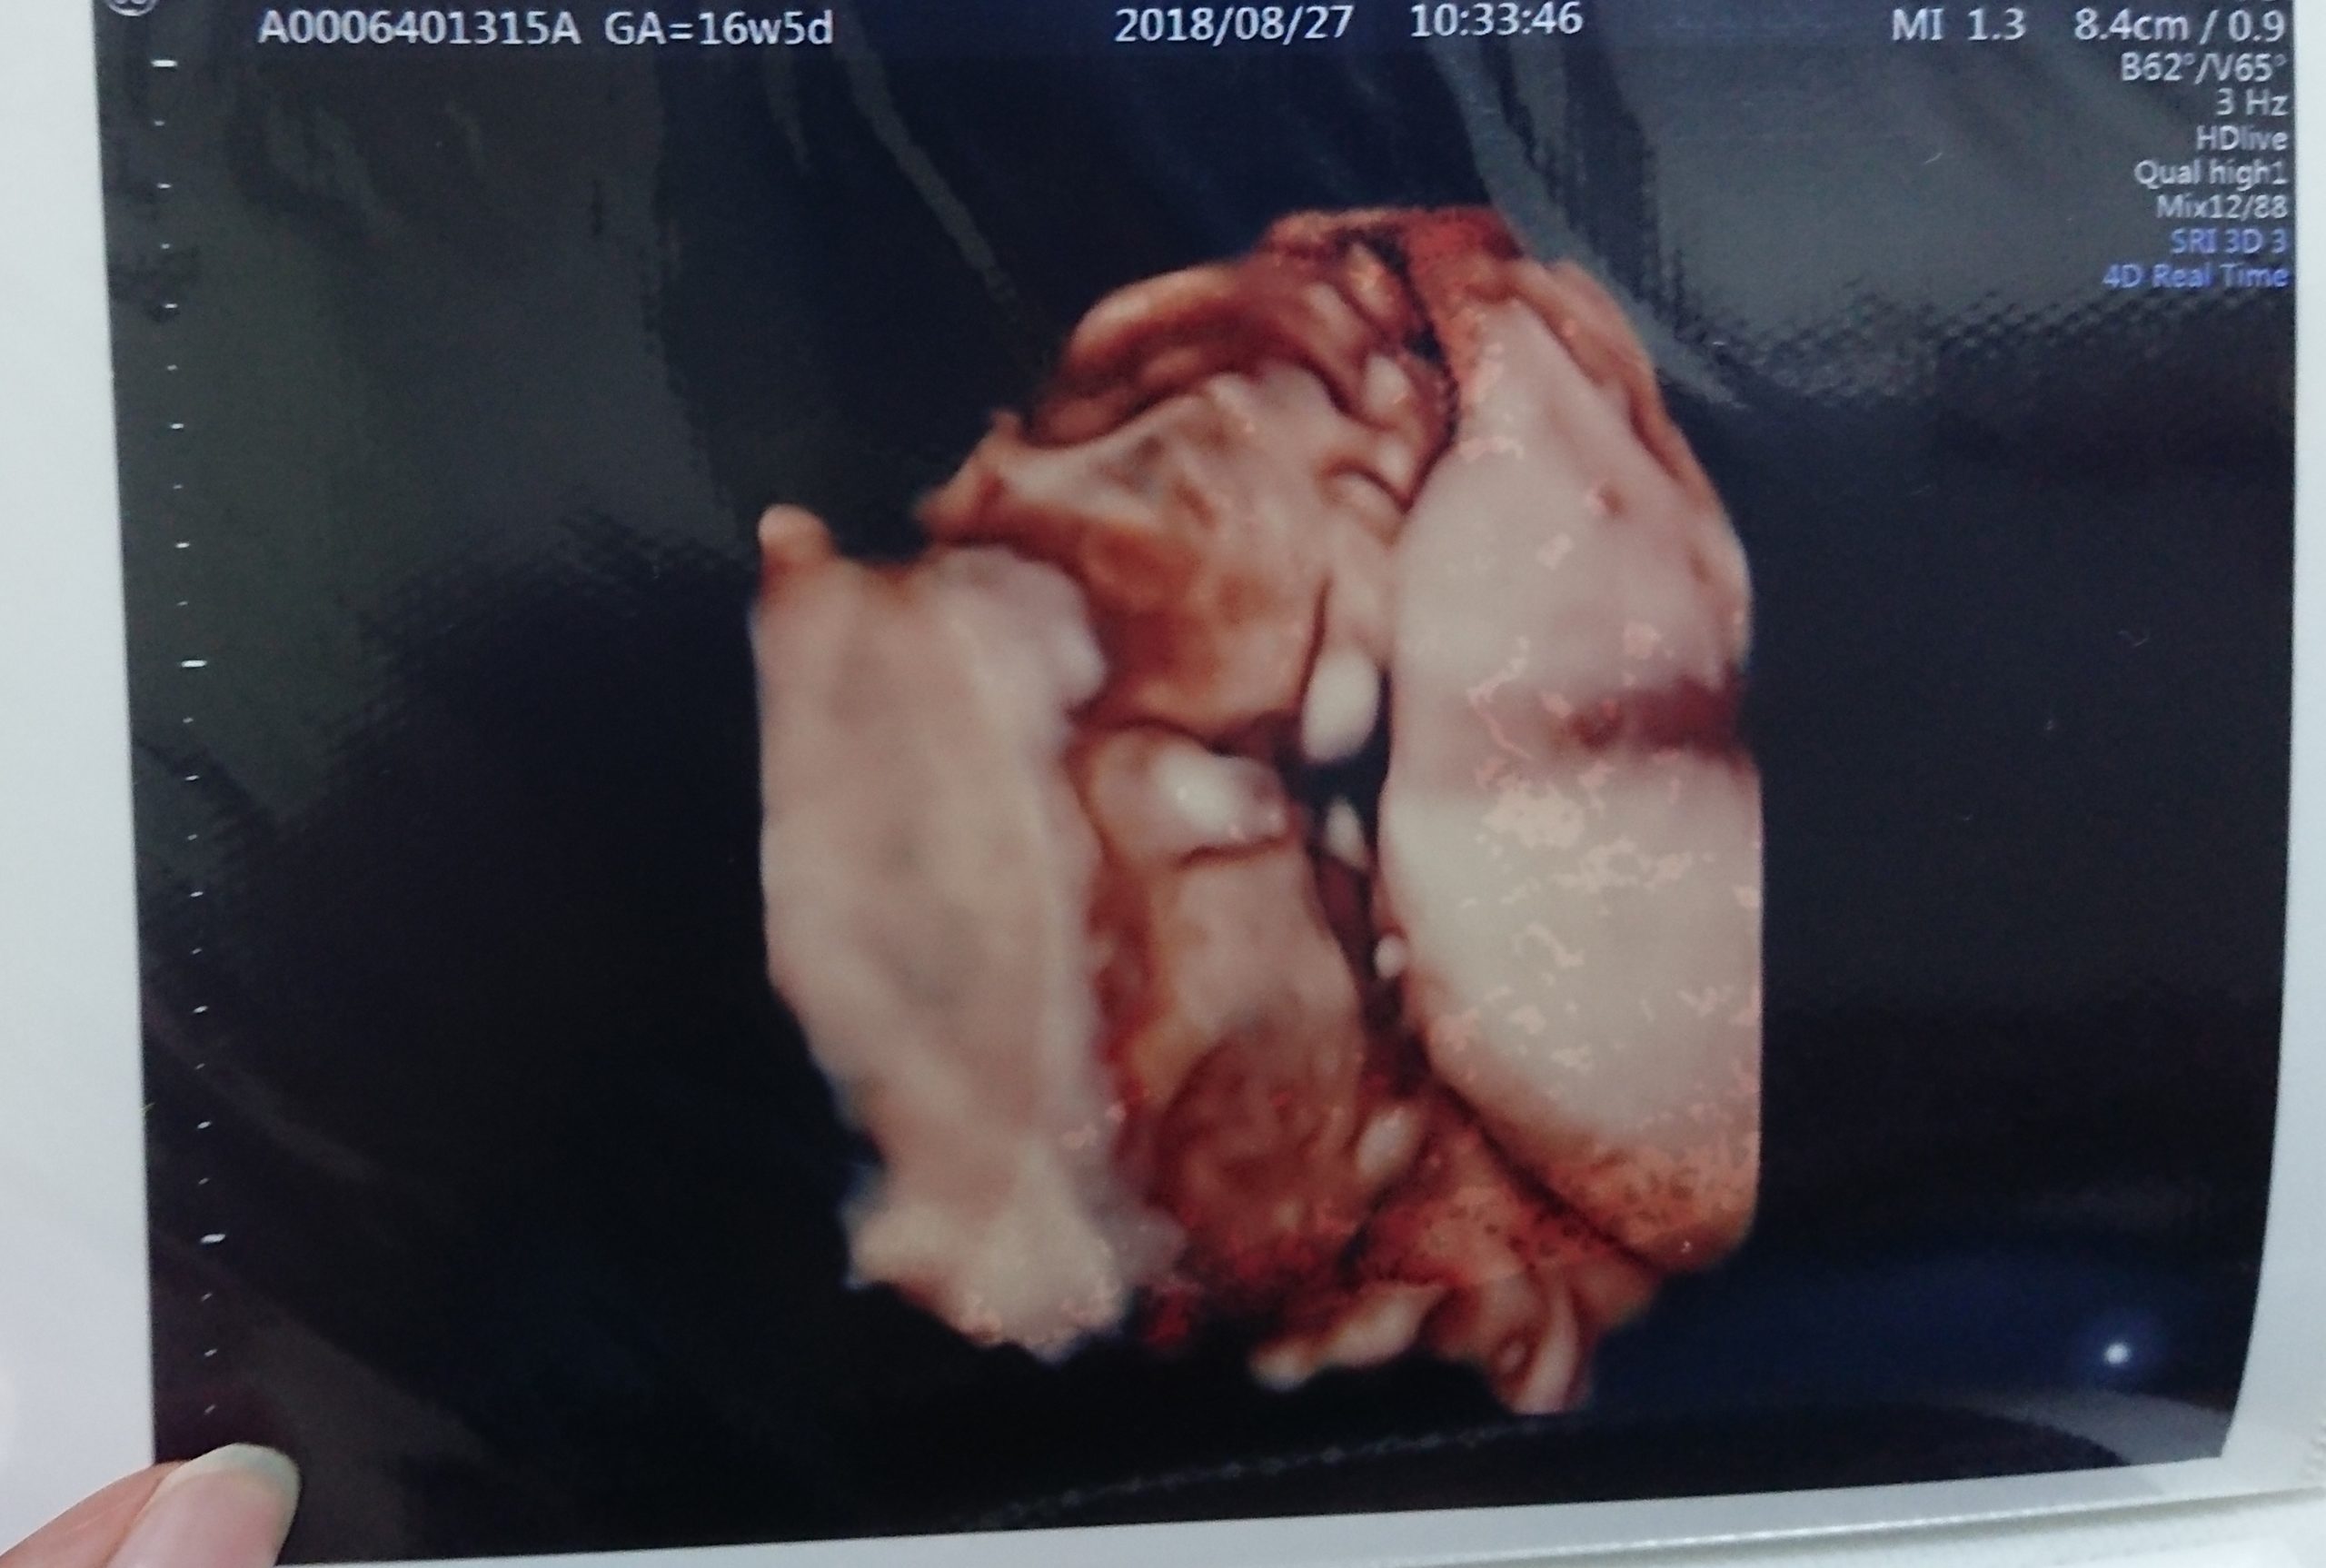

初めて総合病院を受診した後、2週間後にまた検診に行きました。

2018年8月中旬、この時妊娠15週に入っていました。

妊娠16週の時に3回目の妊婦健診がありましたが、前回消失した水腫は再発しておらず

再度、胎児水腫の検査

9月に入り、水腫の再発が無いか検査をしに行ってきました。

結果は再発なし!以前より胎動もしっかりとあり、おなかも大きくなってきていたので